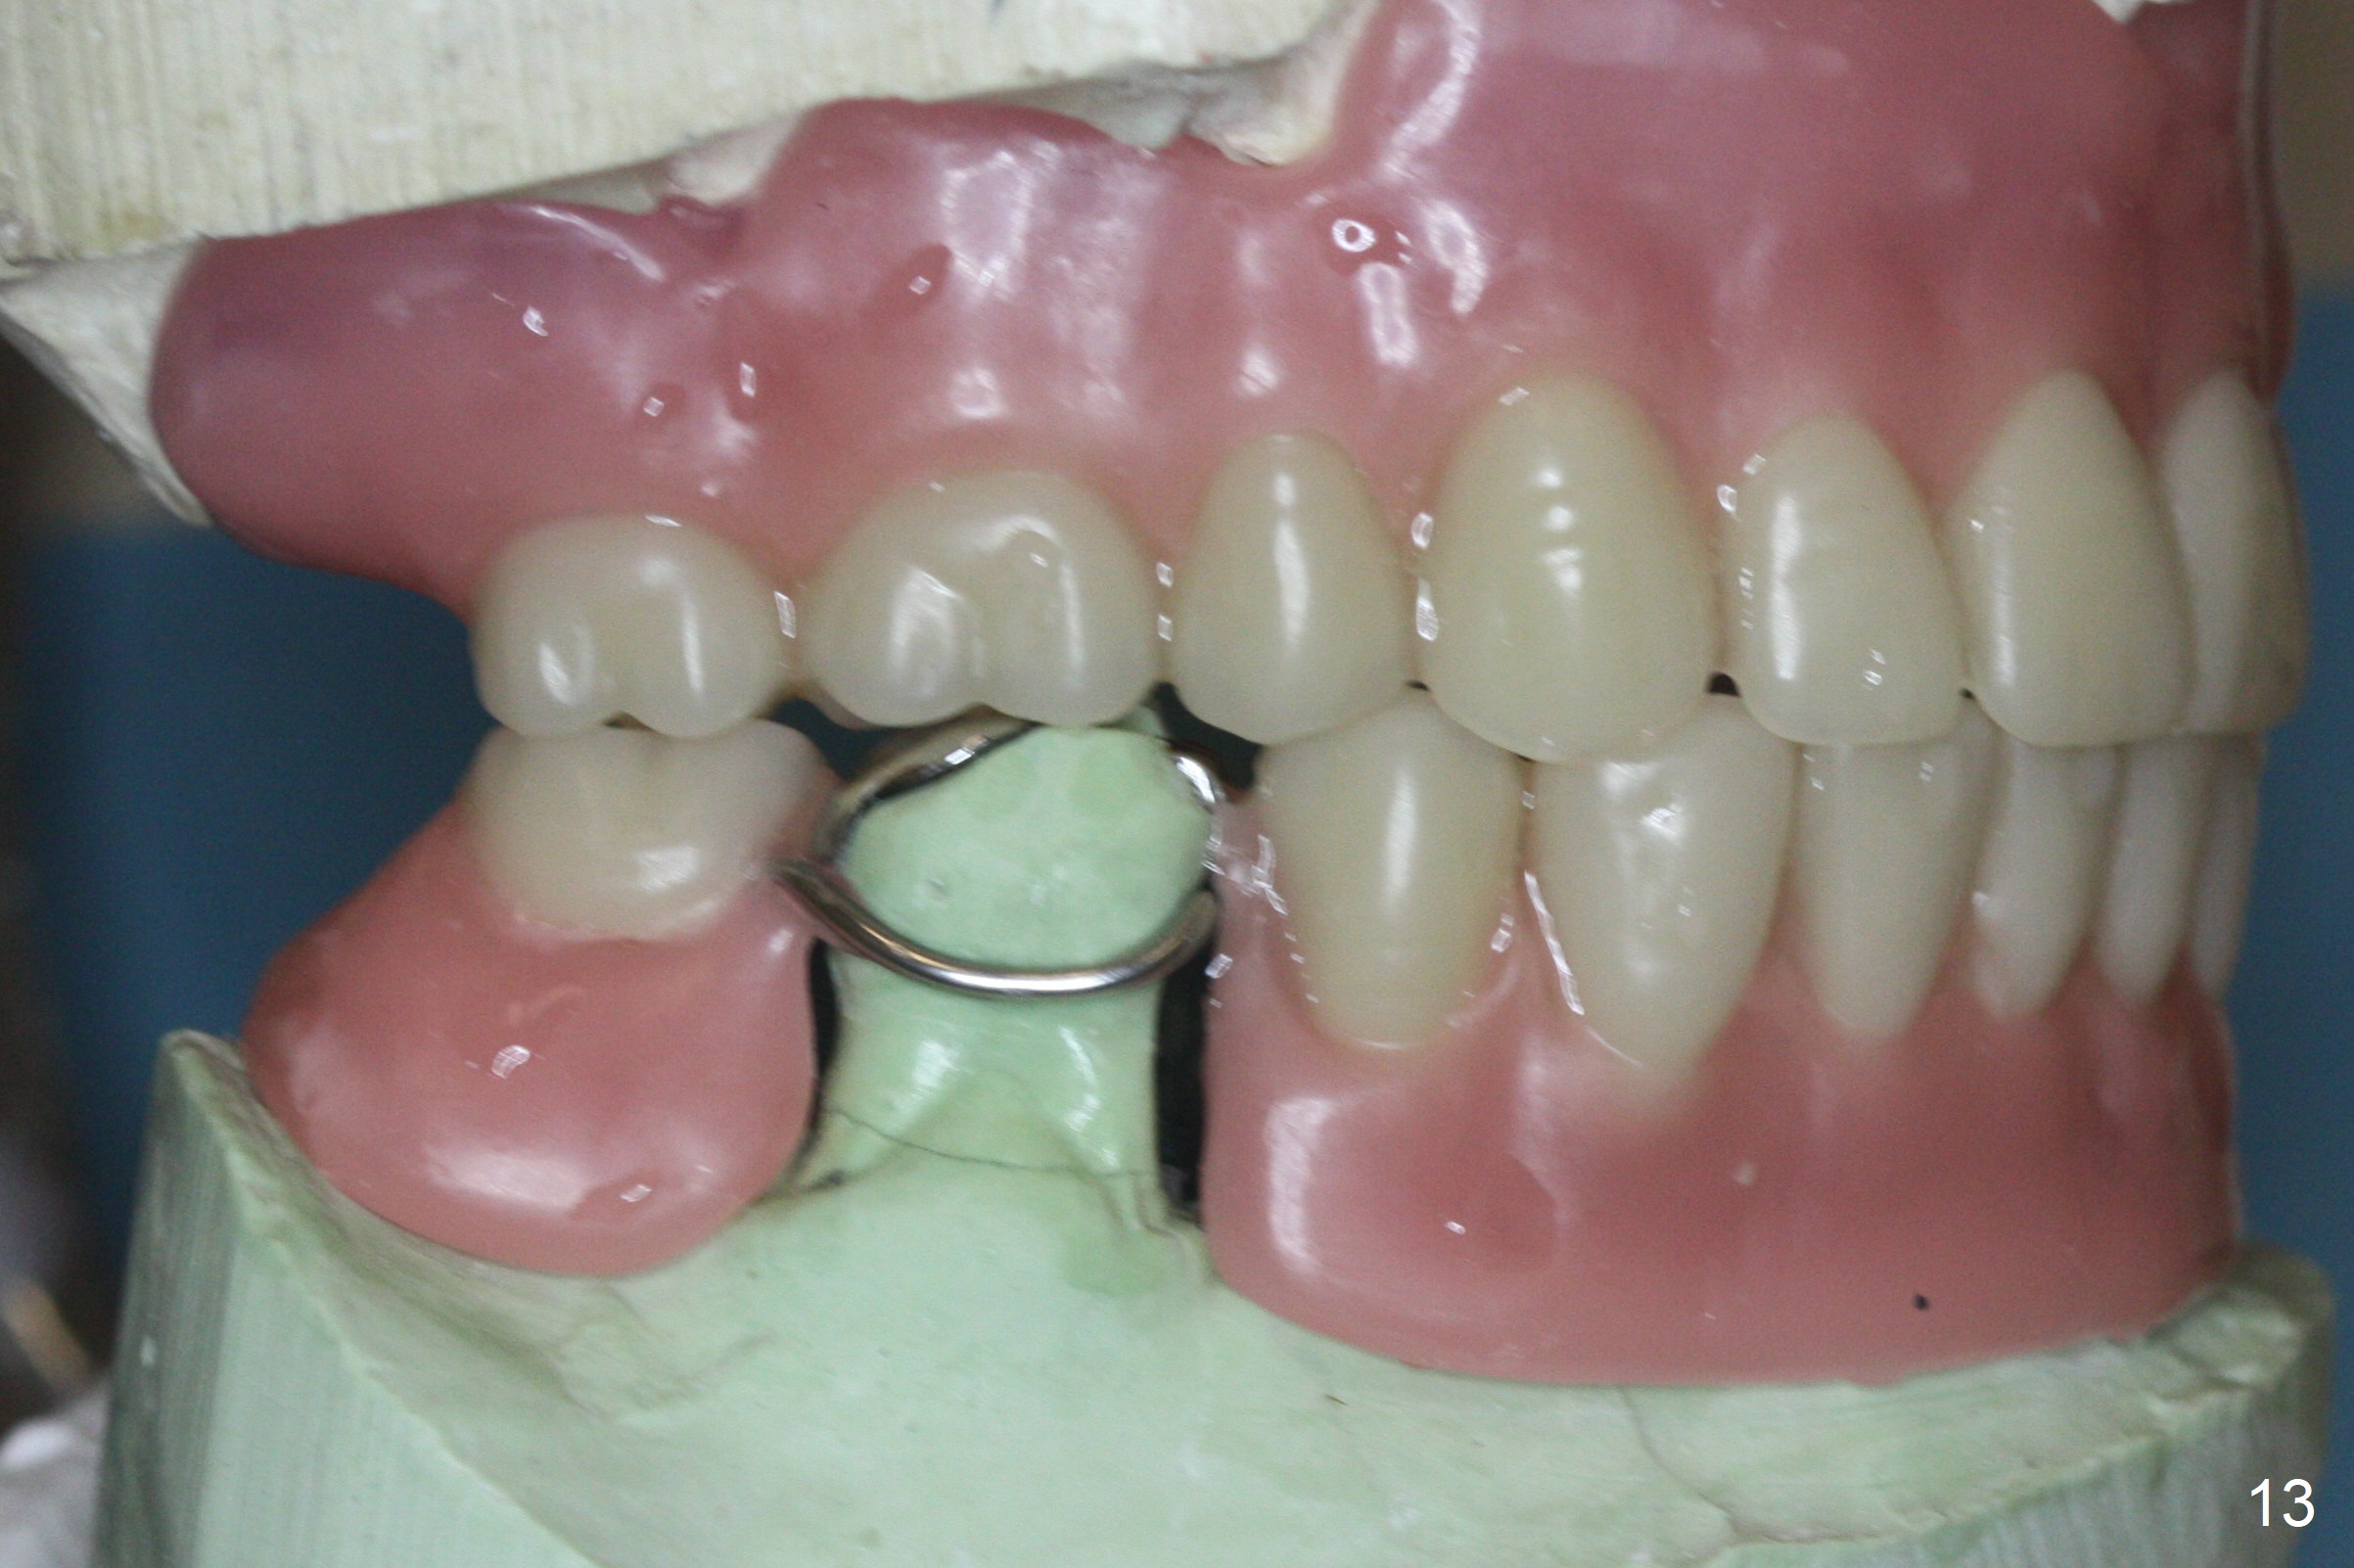

The implant osteointegrates 2 months postop (Fig.9). A pair abutment is placed (Fig.10: 5x4(2) mm) for a provisional (Fig.11). Wax up for final restorations (Fig.12-15). There is no bone resorption 1 year 4 months post cementation (Fig.16). The RPD is doing fine. The implant remains stable 3.5 years post cementation (in spite of open margin), while the other abutment for the RPD (the tooth #30) has mobility with gingival recession.